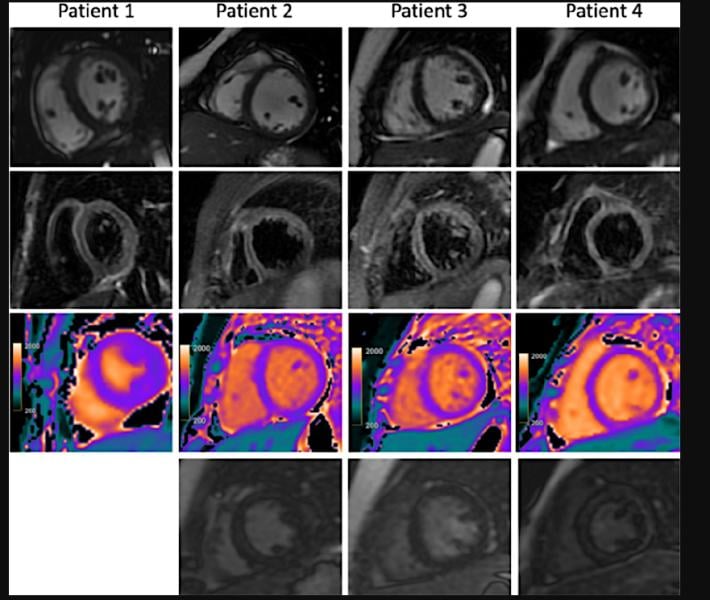

This photo gallery shows the variety of radiological presentations of COVID-19 (SARS-CoV-2) in medical imaging, including computed tomography (CT), radiograph X-rays, ultrasound, echocardiograms and magnetic resonance imaging (MRI). The radiology images show examples of typical COVID pneumonia in the lungs and the numerous complications the virus causes in the body in multiple organs, including the brain, kidneys, heart, abdomen and vascular system.

Ultrasound, especially hand-held ultrasound imaging devices, have become a primary imaging modality for novel coronavirus because of the ease to bag the device and sterilize it after use. CT and mobile X-ray systems are also used as front-line imaging systems for COVID-positive or suspected COVID patients.

The images were collected from physicians, study authors, universities and hospitals, the National Institutes of Health (NIH), the Radiological Society of North America (RSNA), the American College of Radiology (ACR), Centers for Disease Control and Prevention (CDC) and radiology technology vendors.